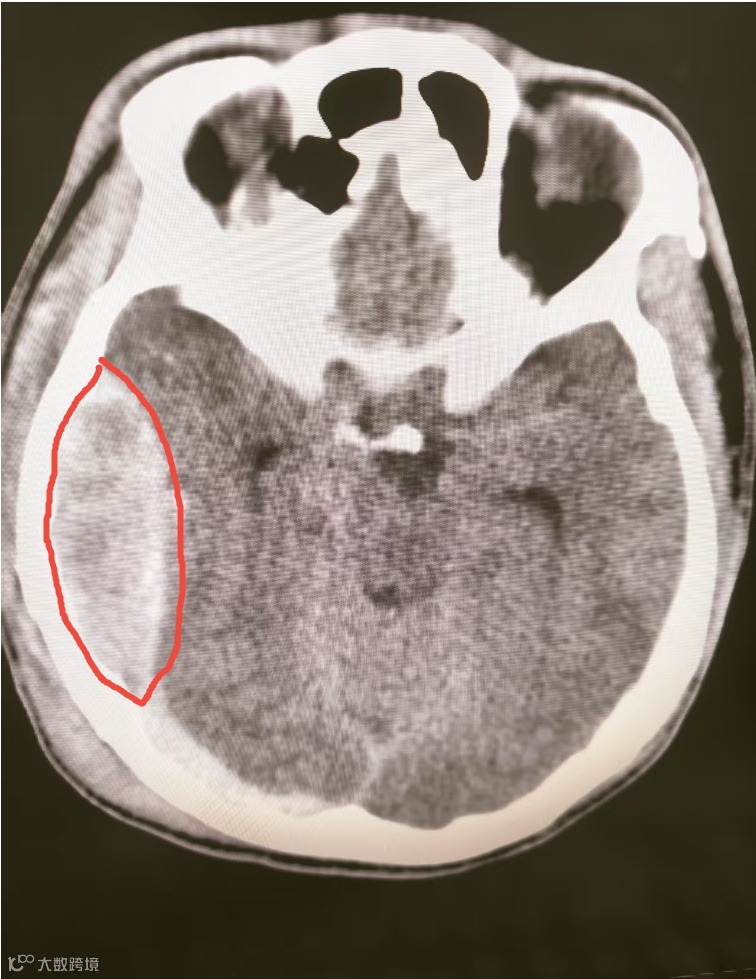

急诊科联系神经医学部会诊,同时急查头+颈椎+颌面部+胸部+全腹部+骨盆CT,综合诊断为重型颅脑损伤!遂拟“头部外伤”收治入神经外科。

颅内血肿

1小时后护士发现患者双侧瞳孔不等大,急复查CT显示出血量增多,颅内血肿达8.5cm*2.5cm约80ml。